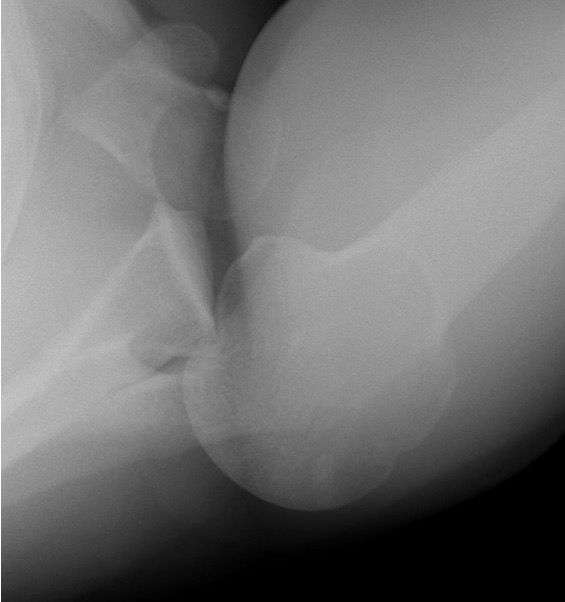

Scapular lateral

Center of the humeral head must be centered on the Y / Mercedes sign

Y is formed by

- coracoid anteriorly

- scapular spine posteriorly

- scapula body inferiorly

Normal scapular lateral

Posterior shoulder dislocation

Posterior shoulder dislocations

Axillary Xray

Diagnostic - humeral head posterior to glenoid with evidence of reverse Hill Sachs